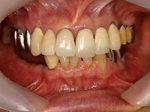

メタルボンド症例

治療前治療前主訴-前歯部の咀嚼不全と審美障害。ブリッジ(固定橋義歯)のために歯を削ったところ 作業模型上のブリッジ作業模型上のブリッジ作業模型上のブリッジ 口腔内装着口腔内装着口腔内装着